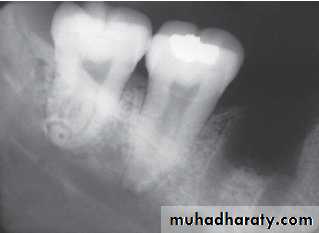

Paramolar blocking the eruption of 3rd molar.

MesiodensDistomolars(4th molar)

Distodens or distomolarParamolar